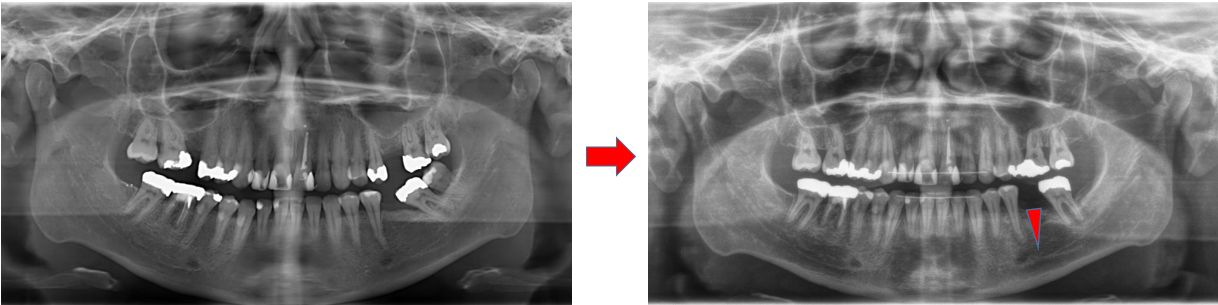

Bestehen Zahnlücken bereits seit längerer Zeit, können die angrenzenden Zähne in den freien Raum kippen. Solche gekippten Zähne sind als Pfeilerzähne – beispielsweise für eine Brücke – ungeeignet und müssen vorab aufgerichtet werden. Eine Lücke führt gegebenenfalls auch dazu, dass der Zahn im Gegenkiefer zu weit herauswächst.